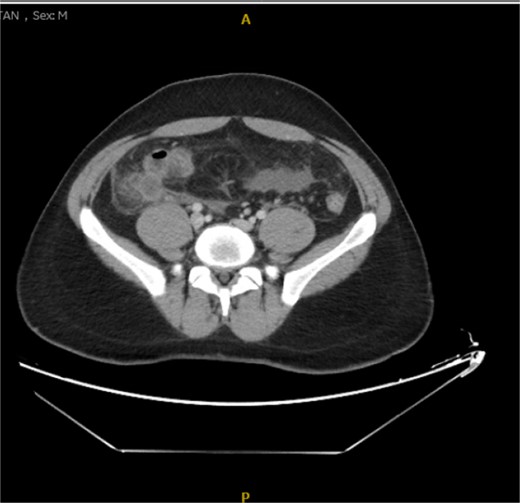

His laboratory tests revealed a white blood cell (WBC) count of 7.8 × 103; all other blood workups were within normal ranges. An abdominal CT scan showed a dilated fluid field in the appendix measuring ~1.8 cm in diameter, with fat stranding, with few areas of decreased well enhancement, and a possible defect in the distal portion of the appendix with phlegm formation (Figs 1–3). All other organs, including the spleen, were unremarkable for any positive findings, with no evidence of free fluid or any splenic injury at the time of the CT scan. The patient was admitted under general surgical care, started on intravenous antibiotics, and was scheduled for laparoscopic exploration and appendectomy. Intraoperative findings included an inflamed appendix and perforation at the midpoint. The patient had an uneventful recovery. The patient was discharged in good condition on postoperative Day 2, with follow-up in the outpatient clinic.

Radiological findings in CT images revealed signs of appendicitis: an enlarged appendicular diameter >6 mm, an appendicular wall thickness >2 mm, mesenteric fat stranding, the presence of an appendicolith, and signs of complications, including perforation or the formation of a peri-appendiceal abscess [10–12]. Careful assessment requires careful medical history taking, physical examination, and radiological investigations with ultrasound or CT scans, which are more sensitive and specific. A high index of suspicion of post-traumatic appendicitis is required because of the rarity of the condition. Treatment includes intravenous antibiotic administration and appendectomy.